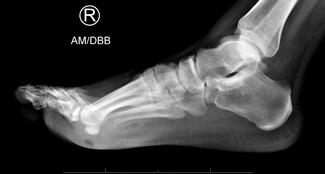

Athletic seasons may bring an influx of children with heel pain into podiatric offices. However, the sedentary results of the COVID-19 pandemic may also cause symptoms in need of evaluation. Here the author outlines appropriate history...

Shoe gear has the potential to play a significant role in the treatment and prevention of lower extremity injuries. Heel pain is a prevalent complaint resulting from several pathologies, including plantar fasciitis and Achilles tendonitis.